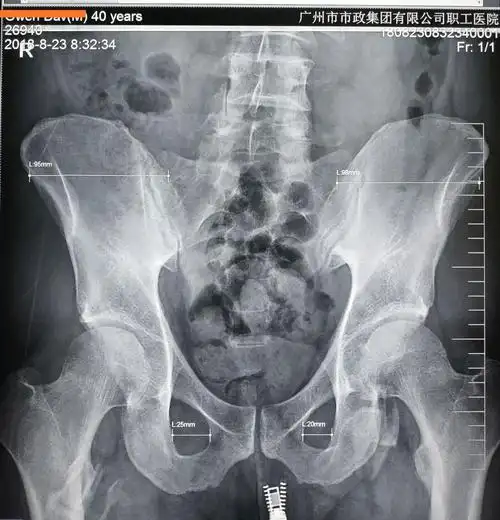

其它 先测量角度,再纠正骨盆旋移 写美篇 x线片:双侧髂骨的